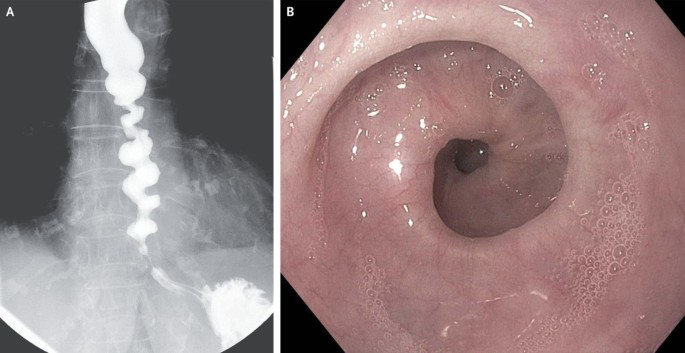

| Diffuser Ösophagusspasmus | Unkoordinierte Kontraktionen | Dysphagie, retrosternale Schmerzen (angina-ähnlich) | Breischluck: „Korkenzieher-Ösophagus“ Manometrie: unkoordinierte Druckspitzen | Spasmolytika, Kalziumantagonisten, ggf. Myotomie |

- Diffuser Spasmus → chaotische Kontraktionen → Korkenzieher